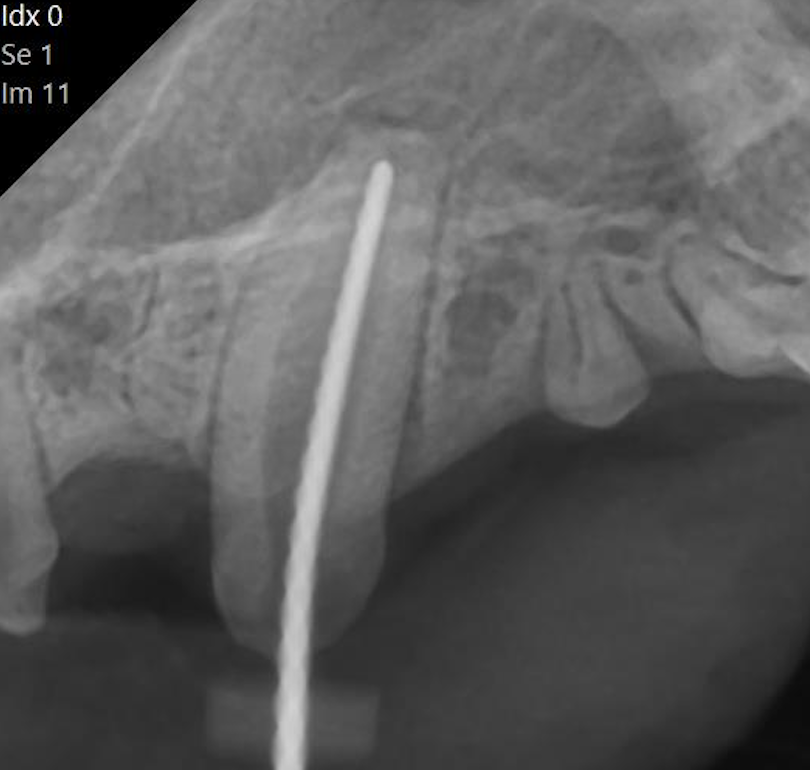

下の写真は犬歯が折れてしまった猫ちゃんです。

レントゲン検査では根尖病変を疑う所見はありませんでしたが、

破折から時間が経ってしまていたため、神経を抜く抜髄治療を行いました。